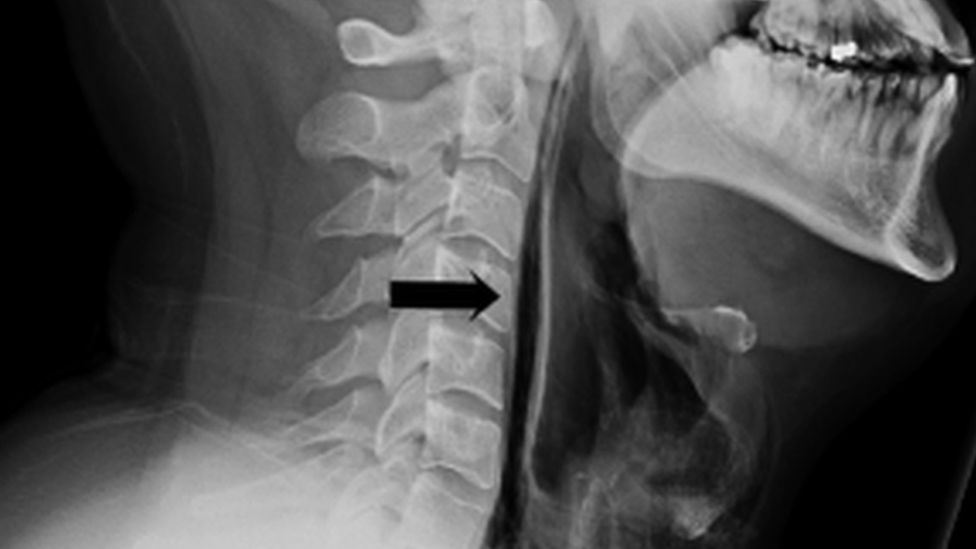

The 34-year-old was rushed to the emergency department at Britain’s Leicester Royal Infirmary and his x-rays revealed that there were “streaks of air” embedded in the soft tissue of his neck – a condition known as subcutaneous emphysema and pneumomediastinum.

In simple terms, the man had literally ruptured his throat by trying to suppress the full force of his sneeze. The air that would have been expelled through the sneeze backfired and instead made its way into his soft tissue as tiny bubbles.

man ruptures his throat after holding in a sneeze Image via Medizzy